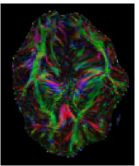

The first eigenvector , also called principal diffusion vector, of describes the predominant diffusion direction, which is parallel to the orientation of the corresponding underlying WM fiber system. Figure 3 shows a visualization of the color-coded MR-DTI data with ellipsoids. The predominant diffusion direction can be directly related to a Green (G), Red (R) and Blue (B) digital color triple. The convention in which the G, R and B color components represent the directions is as follows:

| (6) |

The RGB color-coded directionality maps provide an indication of the direction in which water diffusion is the highest and improve the visibility of different WM fiber bundles.